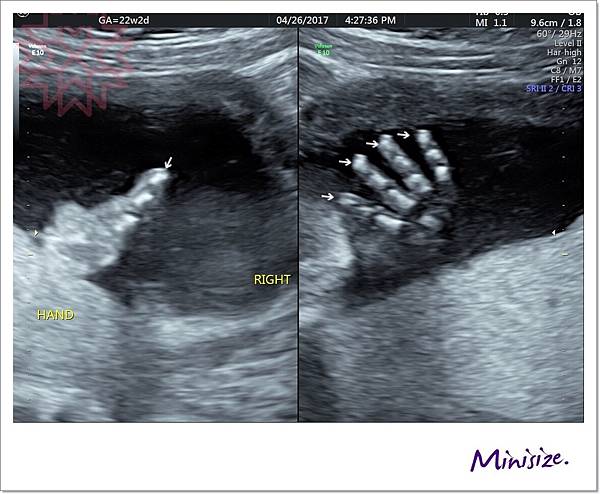

手

剛好我的寶寶手手有摺起來

技術師用兩種不同角度拍照

檢查時會細數1、2、3、4、5 五支手指頭

下兩張左圖都是大拇指 右圖是其餘四指

手指看起來很修長應該是遺傳麻麻

右手